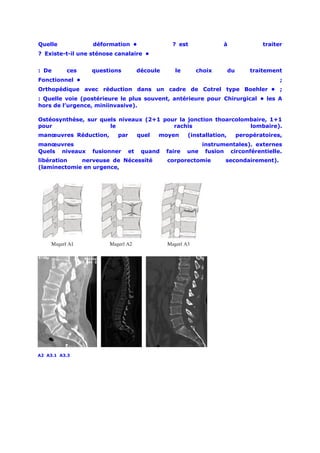

Nous utilisons préférentiellement la classification de Magerl qui est basée sur le

mécanisme lésionnel, comportant 3 groupes principaux subdivisés. Le groupe A

correspond à un mécanisme en compression (les lésions siégeant surtout au

niveau du corps vertébral) allant de la simple fracture du plateau supérieur (A1)

à la burst fracture (fracture comminutive) (A3). Le groupe B correspond aux

fractures par distraction. Il est divisé en trois groupes distincts, les lésions en

flexion-distraction postérieure à prédominance ligamentaire B1, les lésions en

flexion-distraction postérieure à prédominance osseuse B2 et des lésions en

hyperextension avec distraction antérieure B3. Enfin, le groupe C correspond

aux lésions résultant d’un mécanisme en rotation ajouté aux mécanismes des

types A et B. Cette classification a un caractère pronostic, les subdivisions sont

de                     gravité                     croissante.

A2 A3.1 A3.3